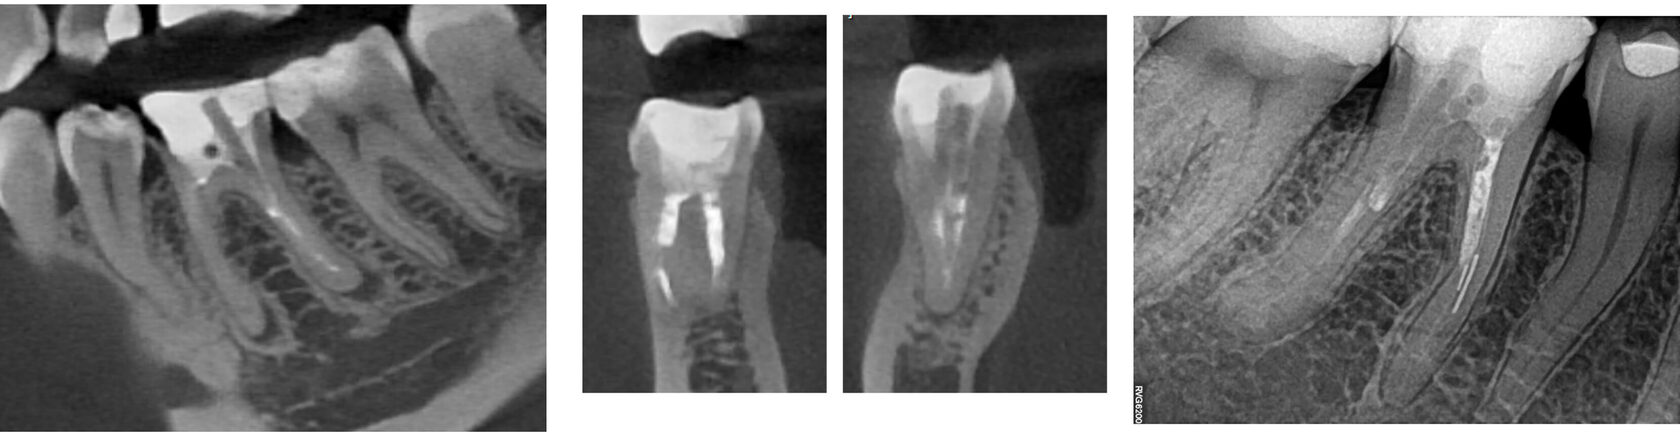

1. The patient presented with tooth #46 (lower right first molar) diagnosed with apical periodontitis, featuring two fractured endodontic instruments in the mesial root canals alongside overprepared canal orifices. Additionally, the distal root contained two misaligned fiber posts that had been cemented non-axially within the canal space, further complicating the endodontic retreatment. (Image 1,2,3)